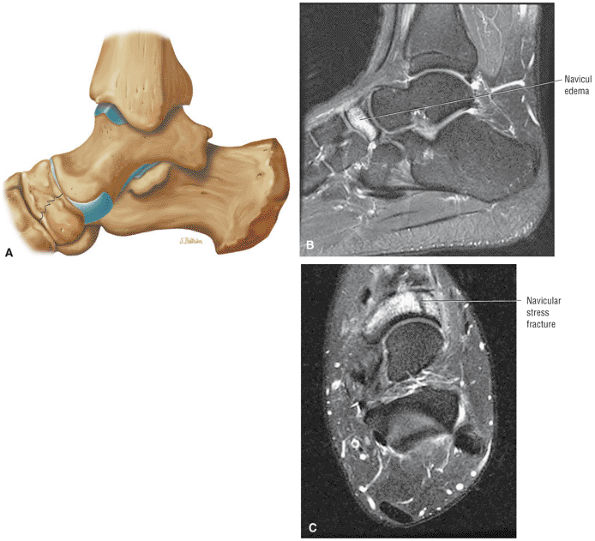

FIGURE 5.26 ● Coronal anatomy of the ankle and foot. (A) The calcaneofibular ligament (CFL) is identified by finding its origin at the inferior tip of the lateral malleolus. The posterior inferomedial course of the CFL is followed on three or four consecutive coronal images moving posteriorly through the ankle, to its insertion on the posterolateral calcaneus. Optimal evaluation of the CFL involves examining its full course on successive images in both the coronal and sagittal plane for tears, sprain, or scarring. (B) The medial cord of the plantar aponeurosis is normally slightly thicker than the lateral cord, and this mild asymmetry in thickness should not be misinterpreted as plantar aponeurosis scarring or plantar fasciitis. On successive coronal images, the course of the plantar aponeurosis should be followed back to its insertion on the inferior calcaneus and evaluated for the presence of thickening, decreased signal suggestive of scarring, increased signal indicative of plantar fasciitis, and tears. (C) Coronal images are optimal for viewing the lateral process of the talus, which is a frequent site of fractures that are occult on plain films. Fractures of the lateral process of the talus are most common in patients with snowboarding injuries. (D) The talar dome and tibial plafond are optimally visualized on coronal images. They are assessed for the presence of subchondral edema and cystic change with overlying chondral abnormalities. Close attention should be directed to the extreme anterior and posterior margins of the cartilage-bearing articular surfaces of the talar dome and tibial plafond to avoid overlooking osteochondral lesions at these locations. (E) The origin of the anterior talofibular ligament (ATFL) is found at the anterior distal tip of the lateral malleolus, and the ATFL is followed anteriorly on two or three successive coronal images to its insertion at the anterior lateral margin of the talus. (F) The deltoid ligament is optimally visualized in the coronal and axial planes. Tears of the deltoid manifest as loss of fiber striation or diffuse amorphous hyperintensity in the ligament on fluid-weighted sequences. Partial tears are more common than complete tears. (G) Focal fatty atrophy and denervation of the plantar flexor muscles of the foot (abductor digiti minimi, flexor digitorum brevis, and abductor hallucis) may indicate neuropathy involving the tibial nerve or its branches. (H) At the level of the anterior aspect of the talus and calcaneus, the peroneal tendons and flexor tendons turn from their cranial—caudal course to travel an anterior-to-posterior course along the plantar aspect of the foot. The distal portions of the tendons should be examined along the plantar aspect of the foot on successive coronal images for evidence of tendinosis and tears. (I) The base of the fifth metatarsal is a common location for fractures and is often visualized within the FOV on ankle MR exams. (J) At the level of the navicular, the flexor digitorum longus (FDL) and flexor hallucis longus (FHL) tendons run side by side, with the FDL medial to the FHL. Anterior to this level on successive coronal images, the two tendons cross, with the FHL medial to the FDL as the FHL courses to its insertion on the great toe. (K) Stress fractures of the navicular are commonly vertical in the midline of the navicular, an appearance that is well characterized on coronal images. (L) Contusions, stress-related edema, fractures, and degenerative arthritis of the midfoot bones and joints are common causes of midfoot pain and are often optimally identified on fluid-sensitive sequences.

Stage I: Subchondral trabecular compression. Radiograph results are negative, bone scans are posi-tive, and marrow edema is seen on MR imaging (Fig. 5.95).

Stage IIA: A subchondral cyst (Fig. 5.96)

Stage IIB: Incomplete separation of the fragment (Fig. 5.97)

Stage III: Fluid around a nondetached, nondisplaced fragment (Figs. 5.98 and 5.99)